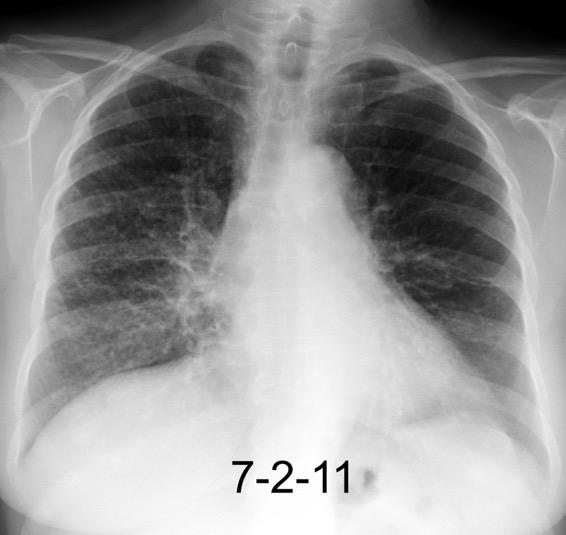

NEUMONITIS POR RADIACIÓN

Neumonitis evidente de 4-12 semanas después de terminar RXT. Fibrosis evidente en 3-4 meses. Estable de 912 meses.

Ca. de mama izquierda. 3/7/09 Radioterapia

La lesión típicamente limitada al campo de irradiación.

Müller NL. 2010

Induce neumonitis. “Tangential beam” para pared torácica.

Jung JI et al. Thoracic Manifestations of Breast Cancer and Its Therapy. Radiographics 2004